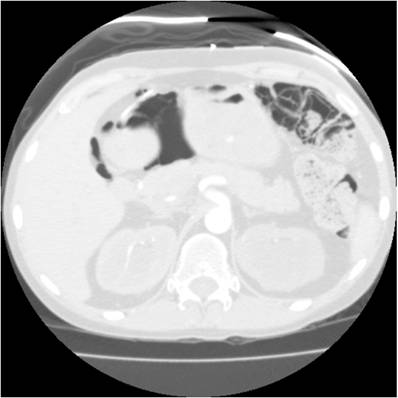

Our pathologic examination demonstrated extensive pneumatosis intestinalis (Figure 2, hematoxylin and eosin [H&E], 40X), and a focus of myeloid (granulocytic) sarcoma at the ileal resection margin. The ileal resection margin contained a small (0.9cm x 0.5cm) serosal nodule composed of an infiltrate of granulocytic precursor cells. Those cells ranged from the most immature blast forms to mature neutrophils - a spectrum consistent with granulocytic sarcoma (also called myeloid sarcoma or chloroma). On the serosal surface, cells formed a discrete mass; they did not involve either the muscular wall or the mucosa of the small bowel. Immuno-histochemistry testing of the mass stained positively for the immature myeloid markers CD 34 (Figure 3, 40X) and CD 117 (Figure 4, 40X); the pattern matched the patient's original diagnostic bone marrow biopsy findings for AML from 3 ½ years previously. This tissue manifestation of AML represented a relapse of the patient's original disease process.

Figure 2

Hematoxylin and eosin [H&E], 40X.